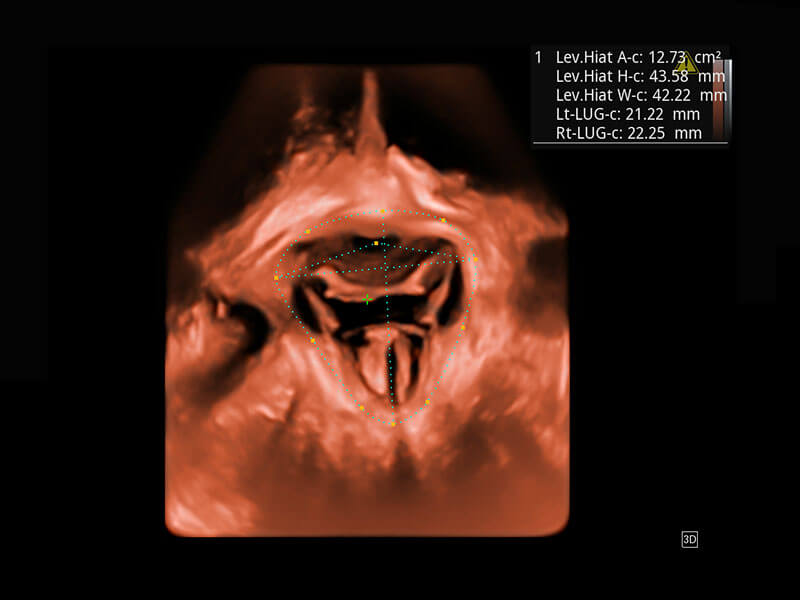

盆底超声

P60为盆底超声检查提供应用方案,多种腔内及腹部容积探头提供从二维、三维到四维的优异图像品质,实时快速三维容积数据获取,专业的测量工具包等人性化设计,为超声医生诊断提供有力保障。

S-Pelvic

能够简化盆底检查的操作流程,可在二维模式及三维成像模式下实现一键自动提取出标准切面、自动识别当前切面、自动测量,提升盆底检查的高效性,同时也能让青年医生快捷的获得准确的检查结果。